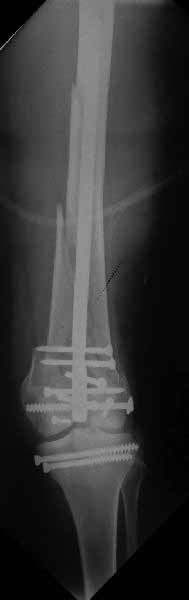

Мне представляется, что конструкция с максимальными прочностными характеристиками будет иметь вид предложенной во вложенном файле. Такую конфигурацию расположения блокирующих отверстий на дистальном конце имеет стержень для большеберцовой кости фирмы ChM. Для бедренной кости такой стержень мне неизвестен. Поэтому в необходимых случаях (хорошо, что такие случаи встречаются не часто), как вариант, мы используем custom made стержень.

Дело, безусловно, не в девятой ложке. Одним из наиболее существенных преимуществ блокированного стержня перед другими металлоконструкциями при диафизарных переломах является его универсальность. Им можно стабилизировать практически любые виды переломов. И с моей точки зрения, уже давно назрела необходимость в разработке такого же универсального стержня для дистальных переломов бедренной кости, возможности которого будут охватывать максимально широкий спектр переломов дистального эпиметафиза бедра. Мне представляется, что конструкция, описанная в моём предыдущем посте, в наибольшей степени учитывает возможные варианты переломов и обеспечит максимальную из возможных прочность их фиксации.

Позволю себе напомнить коллегам ещё раз, что являюсь сторонником антеградного остеосинтеза при переломах дистального эпиметафиза бедренной кости. Такая приверженность основана не на преимуществах внесуставного введения стержня или большем проценте положительных результатов. Она основана на возможности обеспечить блокирование на минимальном расстоянии от суставной поверхности в нескомпрометированной кости и, таким образом стабилизировать максимально низкие переломы. В приведенном Вами случае самый дистальный из блокирующих винтов проведен на расстоянии более 2 см от конца стержня. Из-за того, что к стержню присоединяется кондуктор, на стержне теряется 1-1,5 см его длины, где можно было разместить отверстия для блокирования. И что более важно, вместе с потерянной для этой цели длиной стержня утрачивается для размещения блокировочных винтов, пожалуй, самая ценная часть дистального эпиметафиза бедренной кости. Проблемы дистального блокирования в разных плоскостях, локализации точки ввода стержня при антеградном остеосинтезе – это всё решаемые технические проблемы. Но антеградный остеосинтез низких дистальных переломов бедра при адекватном блокировании в нескомпрометированной кости обеспечивает решение стратегической задачи – стабильный остеосинтез и возможность нагрузки.